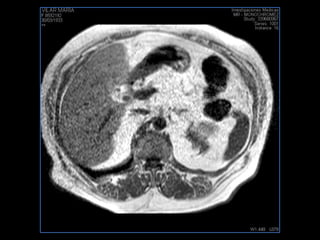

PROTOCOLO abdomen COR T2, AXIAL supresion grasa AX T1 +SAG T2  CON   GADOLINIO :  COR T1+AX T1(DIN) SAT: NO  FASE: RL THK: 6MM  COIL:  GAP: (FACTOR 1.4) 2MM FOV: 40 CM NEX:2 SINCRONIZACION RESPIRATORIA EN 3 O 4 CICLOS ALE